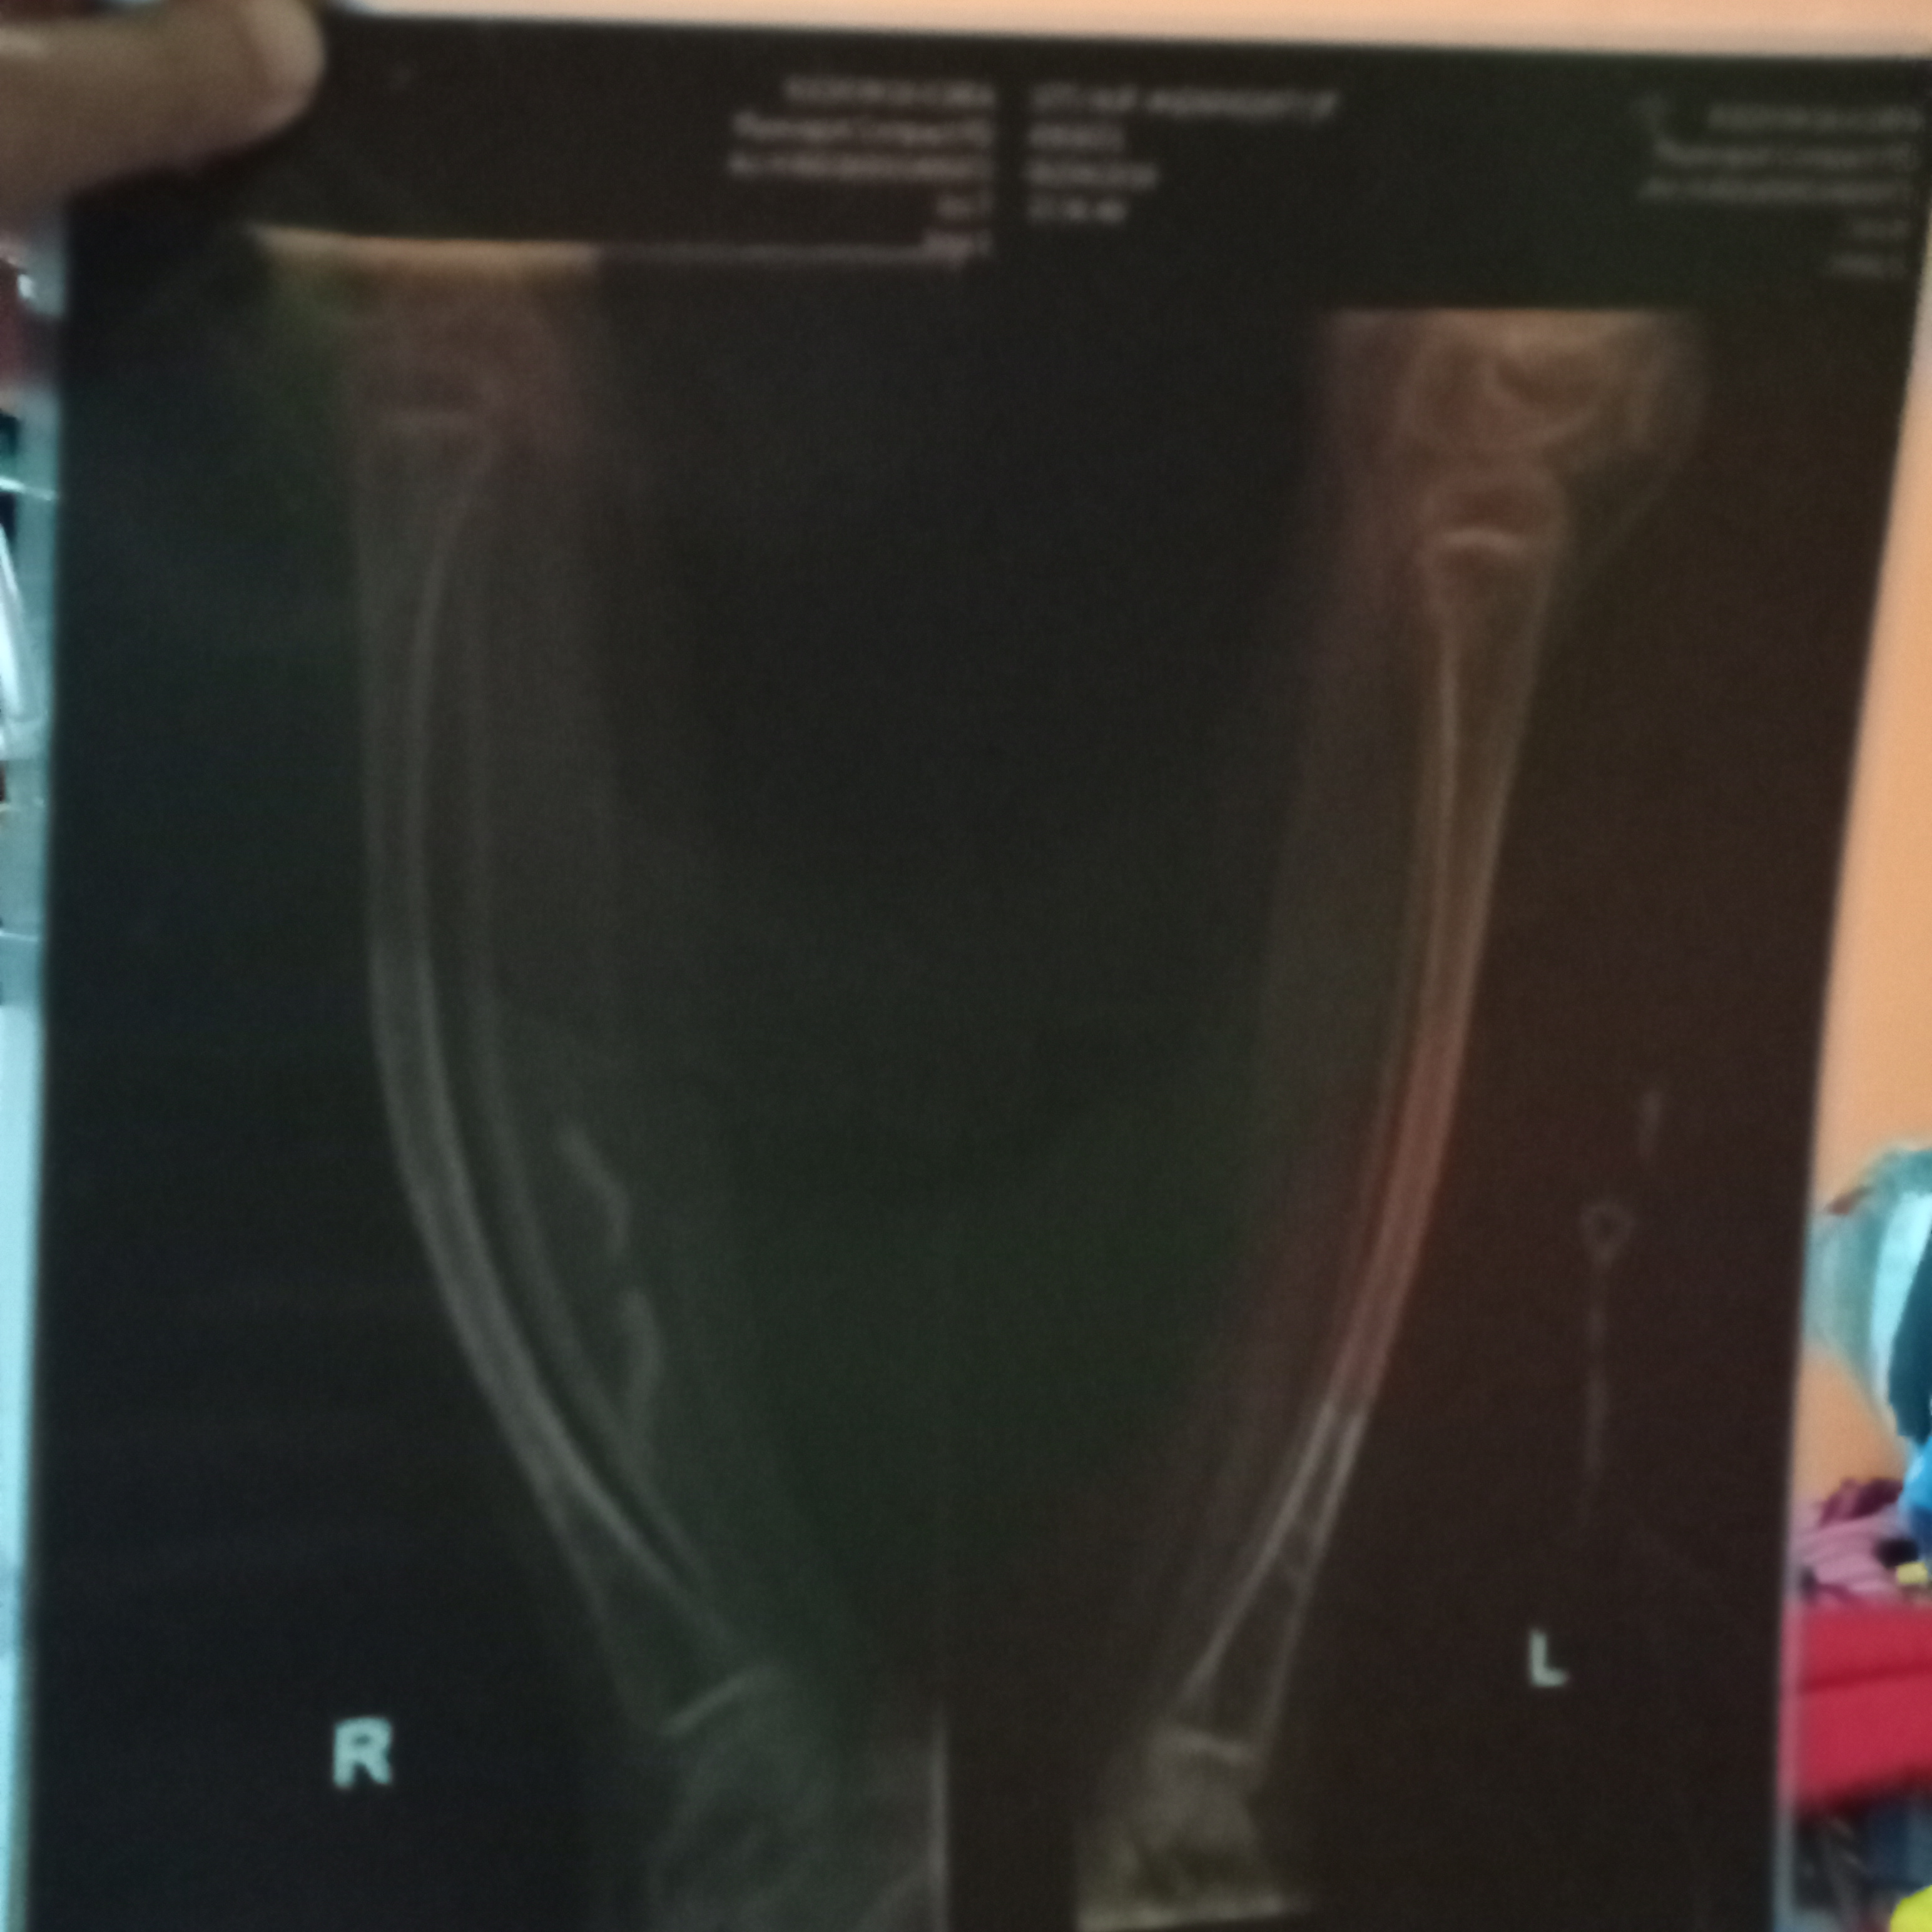

Sebenarnya, anakku disuruh melakukan operasi pasang pen. Tapi, karena anakku tidak berani dan nangis, maka dokter memberi waktu untuk aku membujuknya agar berani untuk dioperasi. Karena, menurut tim dokter kaki kiri dan kanan anakku sudah bowing (bengkok) dan mengkhawatirkan.

Pilihannya ada dua. Pertama, anakku operasi di Indonesia pakai BPJS namun harus setiap tahun bongkar pasang pen karena di RSCM blm ada pen (besi) khusus untuk anak osteogenesis imperfecta. Kedua, operasi di NUH, Singapura dengan pen tanam khusus untuk anak OI. Namun, biaya yang diperkirakan mencapai 1 milyar lebih.

Namun, kaki anza panjang sebelah dan tulang paha kanan kiri bengkok akibat patah tulang berulang kali, sehingga Anza perlu di operasi untuk perbaikan tulang agar Anza bisa berjalan normal seperti teman-temannya.